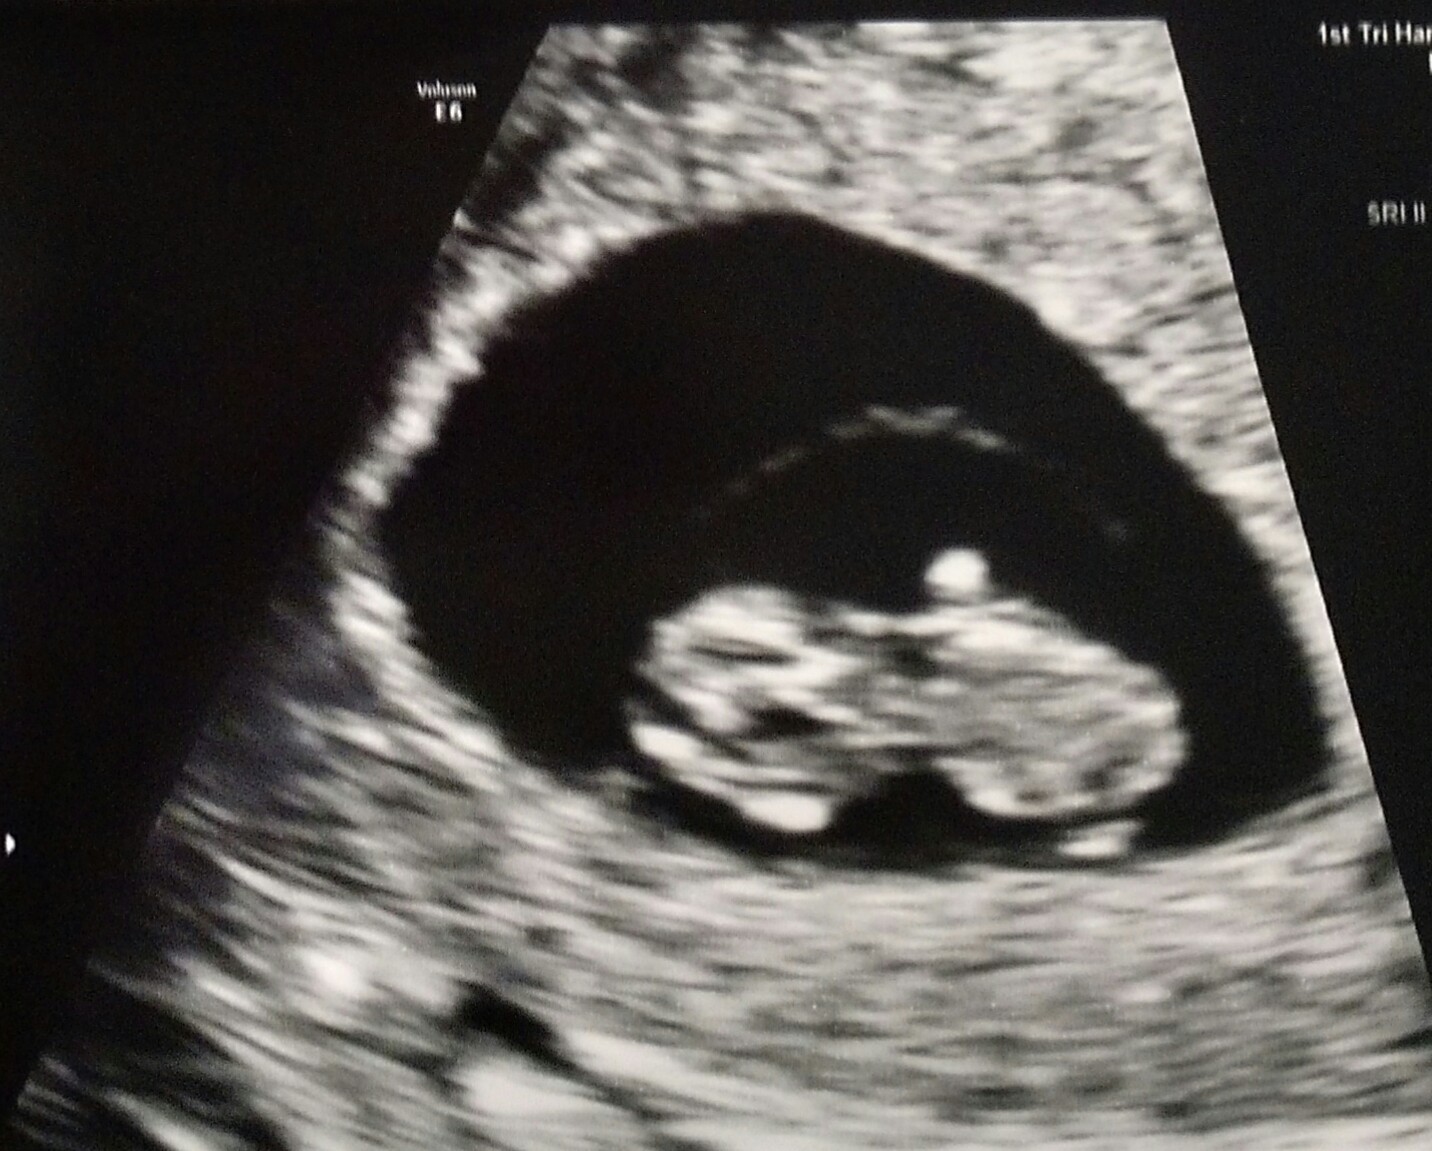

This isn't our first ultrasound, it's actually our 3rd! Our first was 5w5d (and saw a developing HB), then we had one at 6w5d and today was 8w! We will have one every week until I'm out of my first tri (3 previous losses and I have an incredible OB who is looking to keep my anxiety at bay!)